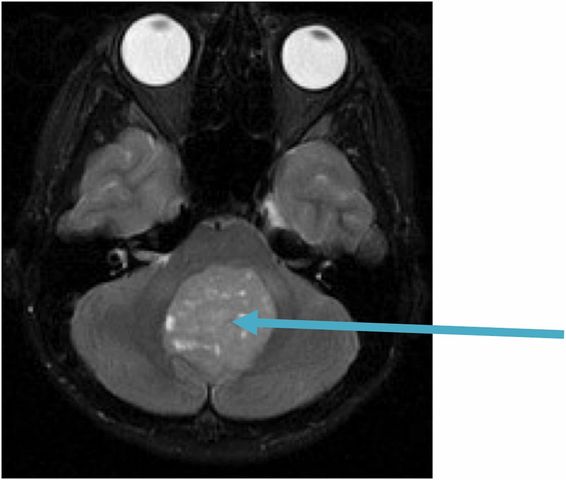

• Primer MRI

Primer MRI

El primer MRI fue hecho a un paciente en una clinica en Inglaterra.